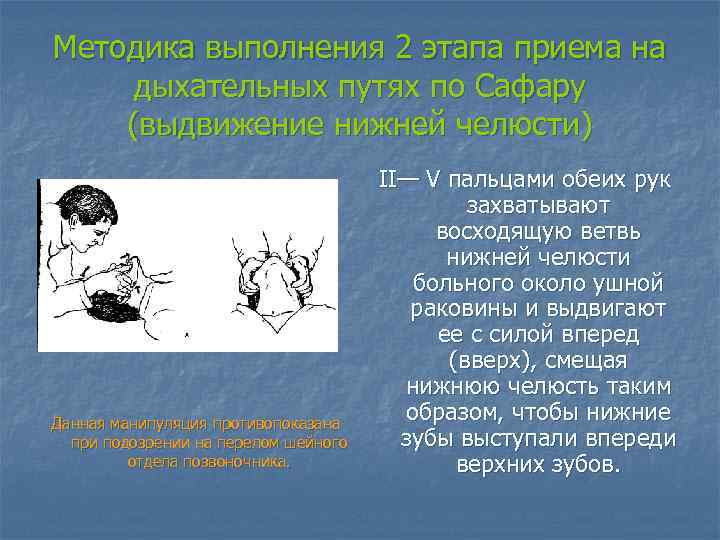

Методика выполнения 2 этапа приема на дыхательных путях по Сафару (выдвижение нижней челюсти) Данная манипуляция противопоказана при подозрении на перелом шейного отдела позвоночника. II— V пальцами обеих рук захватывают восходящую ветвь нижней челюсти больного около ушной раковины и выдвигают ее с силой вперед (вверх), смещая нижнюю челюсть таким образом, чтобы нижние зубы выступали впереди верхних зубов.